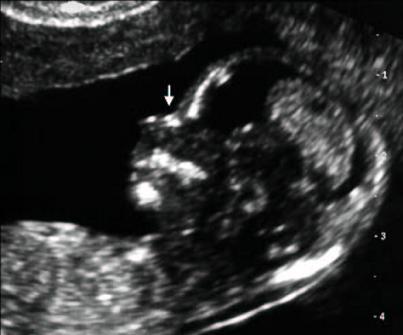

Gracias a un nuevo software desarrollado por un grupo de ginecólogos de Gerona, ahora es posible detectar la posibilidad de que el futuro bebé padezca Síndrome de Down dentro de los tres primeros meses del embarazo.

El software no es todavía 100% fiable, aunque alcanza un alto grado de fiabilidad llegando a alcanzar un 90%, los responsables de su desarrollo, los doctores Josep Sabria, Joan Sabria i Bach y Concepció Bach, han trabajado más de 10 años para obtener esta nueva herramienta que a diferencia de las convencionales, se trata de un sistema que no presenta riesgo alguno y más al no ser invasivo.

El nuevo programa informático se denomina SsdwLab5 y además de poder detectar el Síndrome de Down, detecta el síndrome de Edwards y el Síndrome de Patau. El funcionamiento del software se basa en un modelo matemático estadístico que toma como referencia datos de diversos ámbitos. Sin duda, puede resultar una herramienta eficaz y sin ninguna intención de desmerecer el logro obtenido, debemos decir que el hecho de que tome variables estadísticas, visuales y el margen de error que, aunque mínimo, existe, hace que sea difícil confiar igual que con otras pruebas que rozan el 100% de efectividad.